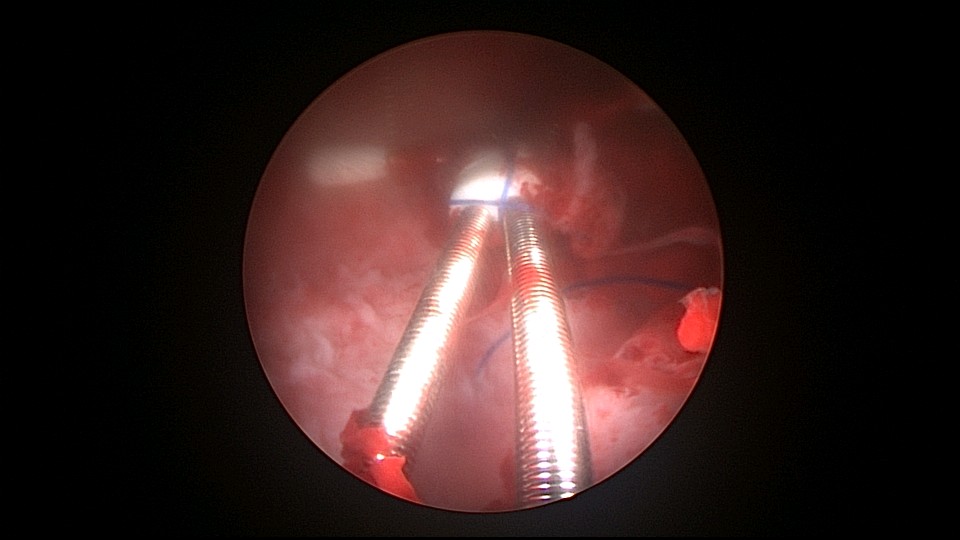

患者38岁,G4P2,剖宫产2次。2025年4月,停经40+天,计划外妊娠,要求终止妊娠并放置节育环,考虑终止妊娠后宫腔大,担心环移位或脱落,要求固定节育环。4-0不可吸收线将节育环缝合固定于宫腔上段后壁,缝合2针形成线圈固定节育环,没有打结推结。利用子宫肌层的卡压,缝合线圈不会自动松脱,形成有效固定,宫颈外口剪断线尾,留线较长,更利于固定。